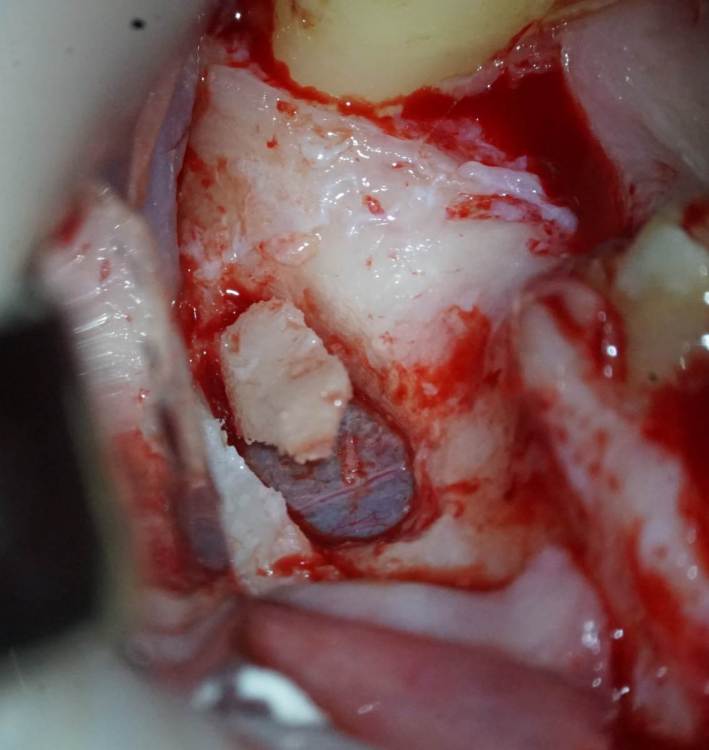

TIGER Опубликовано 8 мая, 2023 Автор Поделиться Опубликовано 8 мая, 2023 Всем привет!планировал удаление,но во время синуса решил использовать фрагмент как клин для стабилизации болта,в итоге совершил ошибку с более медиальной позицией 26,ибо шаблон не изготовил....через 5 мес одел времяхи,т.к будет тотал Ссылка на комментарий